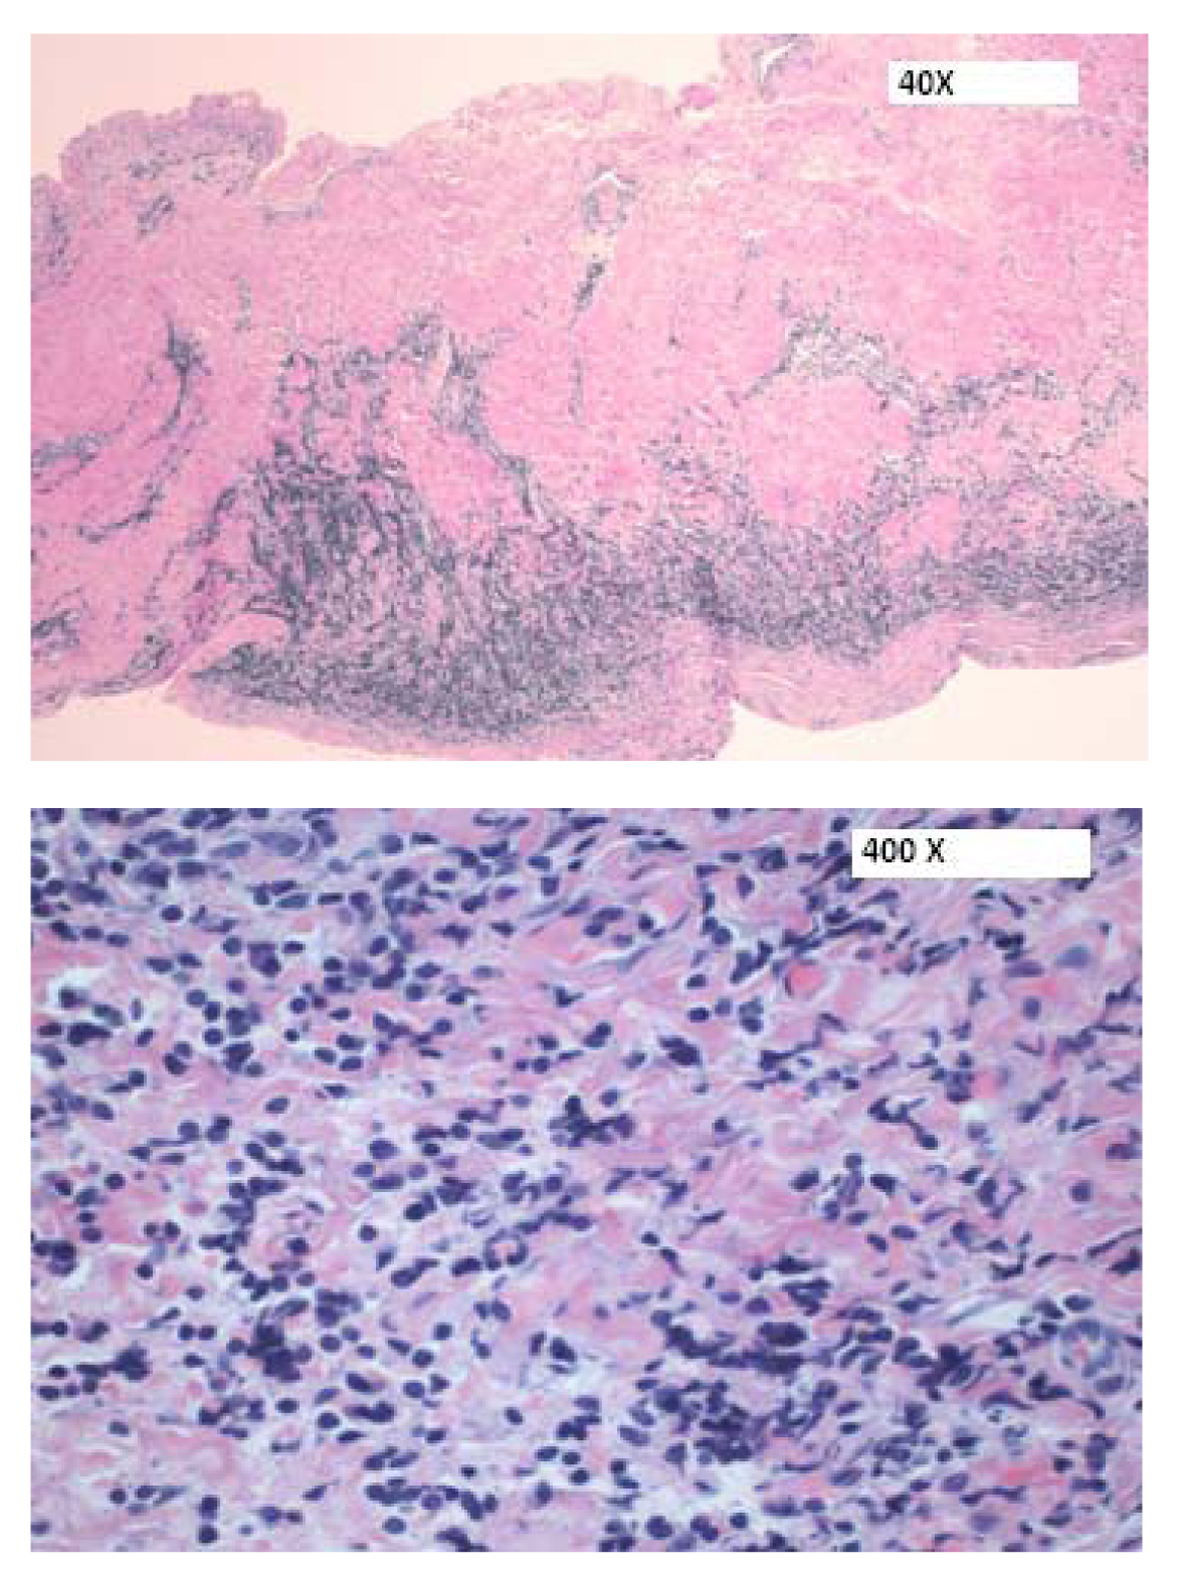

Patient underwent an emergent subxiphoid pericardial window and approximately 1 L of hemopericardium was drained. Bilateral chest tubes were also inserted for pleural effusion. Following drainage of his effusions (pericardial and pleural), patient’s condition improved significantly. Histopathology (pericardial tissue) results were compatible with a precursor T-cell LBL (Fig. 5, 6).

![]() Click for large image | Figure 5. H&E sections of the pericardium showing a focal infiltrate of medium-sized cells within the pericardial wall. |